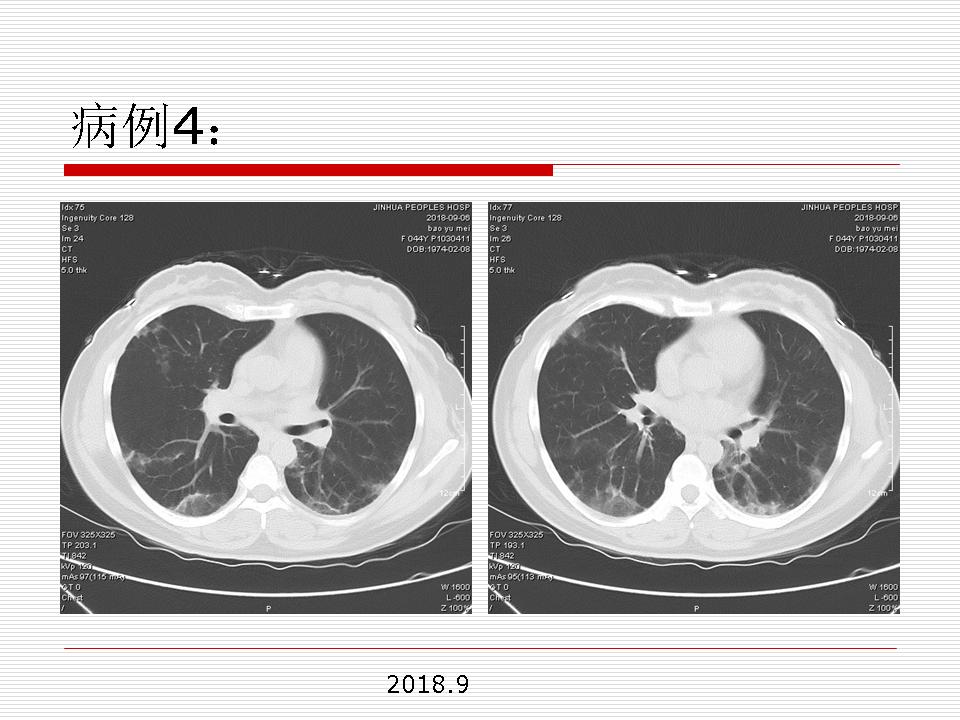

肺部阴影永恒且最重需要鉴别的是:到底是炎症还是肿瘤?但临床的病例中的影像表现难以界定或有些肿瘤特征,同时又有些炎症特点是非常常见的情况。作为临床医生我们怎么去总结分析,并找到之所以是炎症或之所以是肿瘤的细微差别或特点非常重要,也非常有用。2019.12.7浙江省2019年胸心外科学学术年会在宁波召开时,我的临床病例分析与经验总结<那些像肺癌的炎症与像炎症的肺癌>获得在大会交流的机会,以下为该PPT的内容,与你分享,希望对同道有益,有借鉴与启迪。若有探讨与进一不完善的建议,欢迎文末留言讨论: